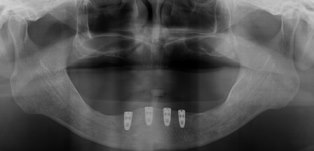

残念ながら上アゴの歯は歯を残したとしても返ってその部分を支点にして入れ歯が動いてしまい、あまりいい結果をだせないので抜かせて頂きました。今日はまずは下顎に4本のインプラントを植えさせていただきました。

3ヶ月後には2回目のオペを行い最終的には義歯タイプの上物を入れる予定です。